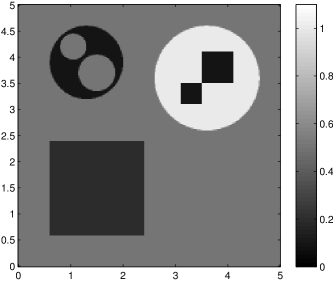

The data (see Figures 1 and 2) was generated in the diffusion model (1.2) using self-written (linear-basis) finite element code in MATLAB. For both examples, we took and used a uniform boundary condition . The simulated data were generated on a -grid and then down-sampled (by averaging) to to avoid inverse crime. After that, Gaussian noise with different intensities (standard deviations of and of the average signal value ) was added to the data.

Reconstruction results and error profiles at different noise levels can be seen in Figures 3 and 4. In both examples, the noise-free reconstructions are very accurate and contain mostly smoothing error. In the low-noise reconstructions, due to the fact that more regularization is necessary, some of the parameter variation is underestimated. In the high-noise examples, most detail in is lost since a lot of regularization is required to get reasonable results. The fine detail in can, however, still be recovered very accurately in both examples.